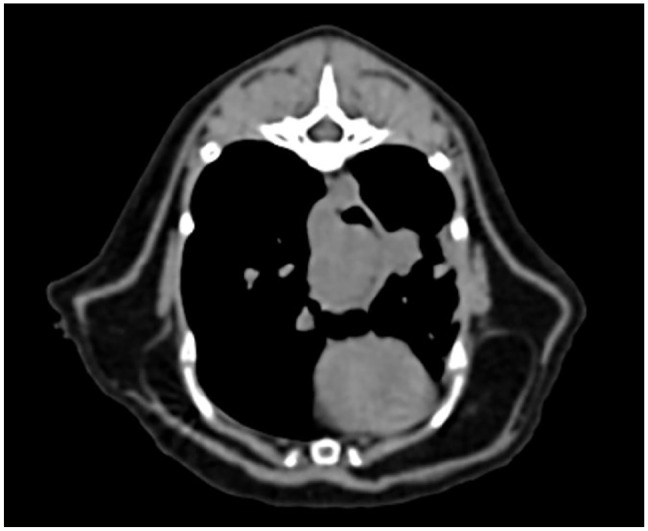

Case summary: A 15-year-old male castrated domestic shorthair cat was presented for acute lethargy, vomiting and hyporexia. Abdominal and thoracic radiographs revealed a caudal thoracic/esophageal soft tissue opacity with concern for an esophageal mass or an esophageal foreign body. Esophagoscopy confirmed the presence of a large, irregular, mid-esophageal mass. Laser ablation using esophagoscopy was utilized to debulk the mass. Approximately 80% of the mass was removed without complication and an esophagostomy feeding tube was placed. The cat was discharged the same day of the procedure. Histopathology and immunohistochemistry staining were consistent with a plasma cell tumor. Recheck esophagoscopy 2 weeks after the procedure revealed no evidence of regrowth and resolved clinical signs in the patient.